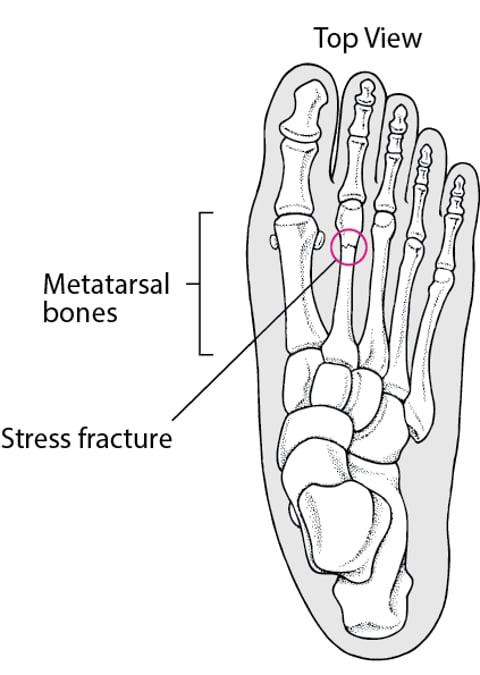

https://adsense.google.com/adsense/u/1/pub-9161951367286286/myads/sites/preview?url=notion6988.tistory.com 🏃‍♂️ 러닝 후 생긴 ‘발등’ 통증… 2주 넘으면 근육통 아닌 ‘이것’